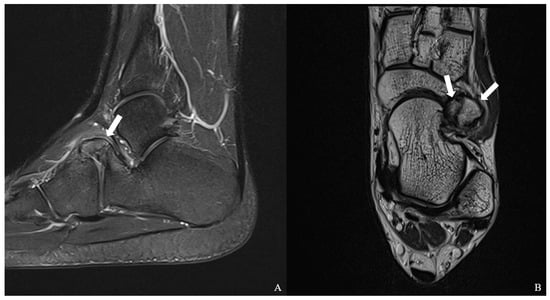

Multiple Calcaneus Secundarius Ossicles Presenting with Anterior Foot Pain: A Case Report Highlighting Characteristic Imaging Features

by Ki Jin Jung, Eui Dong Yeo, Jeong Han Nam and Woo Jong Kim

Background: Calcaneus secundarius (CS) is an accessory ossicle located at the anterior aspect of the calcaneus and is typically an incidental and asymptomatic radiographic finding. However, it may become symptomatic following trauma or repetitive mechanical stress and can mimic anterior calcaneal process [...] Read more.

Background: Calcaneus secundarius (CS) is an accessory ossicle located at the anterior aspect of the calcaneus and is typically an incidental and asymptomatic radiographic finding. However, it may become symptomatic following trauma or repetitive mechanical stress and can mimic anterior calcaneal process fracture or tarsal coalition, leading to diagnostic confusion. The presence of multiple independent CS ossicles represents a rare morphological variant and a potential source of diagnostic ambiguity. Methods: We report the case of a 19-year-old male soldier who presented with progressive anterior foot pain following soccer activity without a clearly identifiable traumatic event. Radiographs, computed tomography (CT), and magnetic resonance imaging (MRI) were performed to evaluate the underlying pathology. Results: CT demonstrated two separate, well-corticated accessory ossicles adjacent to the anterior calcaneal process without bony continuity. MRI revealed focal bone marrow edema (BME) at the calcaneus–ossicle interface, suggesting mechanical irritation at the fibrous connection. Due to persistent symptoms and concordant imaging findings, surgical excision was performed, resulting in immediate pain relief and return to full daily and sports activities without recurrence at the 1-year follow-up. Conclusions: Multiple CS ossicles may produce fragment-like imaging appearances and increase the risk of misdiagnosis. Recognition of characteristic imaging features, particularly well-corticated ossicles and focal BME at the ossicle–calcaneus interface, together with clinical correlation, is essential for accurate diagnosis and appropriate management in patients with persistent anterior foot pain. Full article

Figure 1